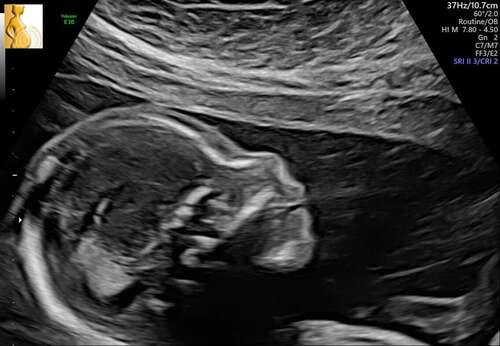

Wowww, richtig groß oder❤️ süßes Profil

Vielen Dank. Für die Woche war er genau richtig. Hat auch ordentlich geturnt.